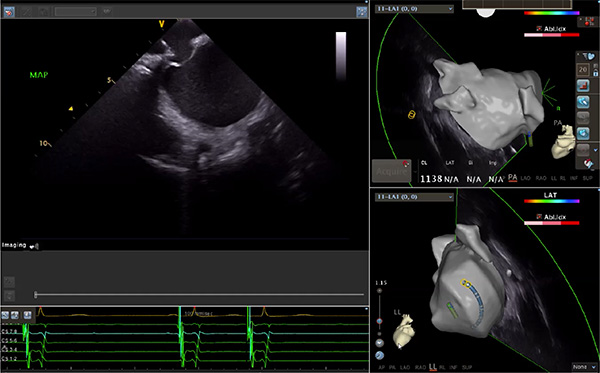

超聲心動圖技術(shù)包括常規(guī)經(jīng)胸超聲(TTE)、經(jīng)食管超聲(TEE)、心腔內(nèi)超聲(ICE)、超聲聲學(xué)造影(MCE)、三維超聲心動圖等,ICE是一種新興技術(shù)——將微型的換能器安裝在心導(dǎo)管的尖端,經(jīng)由外周血管輸送至心腔內(nèi)部,換能器發(fā)射聲波,對心臟及其鄰近組織進行實時高質(zhì)量成像和(或)血流動力學(xué)測定的超聲成像技術(shù)?;诓煌募夹g(shù)原理,心腔內(nèi)超聲導(dǎo)管被分為兩類:機械旋轉(zhuǎn)式超聲導(dǎo)管和相控陣超聲導(dǎo)管。目前,臨床上主要應(yīng)用的是相控陣超聲導(dǎo)管,ICE成像通過術(shù)者旋轉(zhuǎn)導(dǎo)管及操縱導(dǎo)管手柄上的兩個旋鈕來完成。

隨著心腔內(nèi)超聲的應(yīng)用更廣,性能也在逐漸優(yōu)化,已從二維成像轉(zhuǎn)變?yōu)?strong>三維成像,極大增強了引導(dǎo)及可視化能力。二維心腔內(nèi)超聲支持雙平面或三平面成像,可顯示兩個或三個不同的平面視圖,但醫(yī)生需將這些圖像在腦海中重新構(gòu)建為三維解剖結(jié)構(gòu)。三維心腔內(nèi)超聲則可直接呈現(xiàn)三維解剖結(jié)構(gòu)圖,便于醫(yī)生更輕松地開展手術(shù)。按照產(chǎn)品發(fā)展方向,預(yù)計心腔內(nèi)超聲還將向更清晰、精準(zhǔn)、多功能等方向發(fā)展。